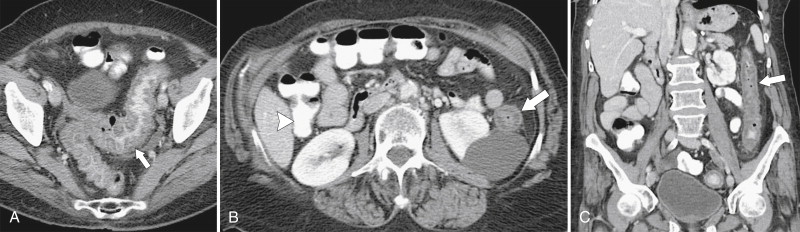

Figure 5-37, Axial ( A and B ) and coronal ( C ) contrast-enhanced CT in a 66-year-old woman with diffuse left colonic mucosal thickening ( arrows ) due to ischemic colitis. Note the normal right colon ( arrowhead ).

Figure 5-38, A through C, Coronal and axial contrast-enhanced CT in a 62-year-old man with a transverse colon adenocarcinoma ( arrows ) with proximal ascending colon mucosal thickening due to secondary ischemia.